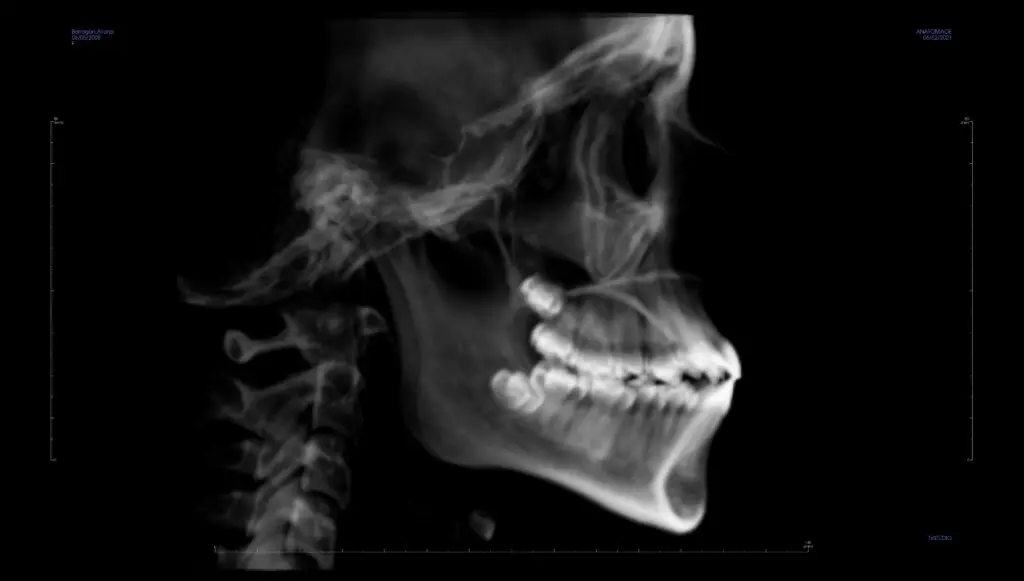

Traditionally, orthodontic diagnosis and treatment planning has been done with 2-dimensional imaging using a panoramic x-ray, generally showing what teeth are present and where they are, and a cephalometric x-ray, which is a side view that gives a general idea of jaw positioning. Cone Beam Computed Tomography, or CBCT, is a 3D x-ray that shows so much more information in a single image, with much higher accuracy than ever before.

Let’s compare the 2D and 3D images in the cases below. You will be able to see the benefits of 3D imaging.

Case 1: Need for extractions. In the 2D x-rays, it looks like there’s plenty of room to fit all of the teeth in the bone. But when looking at the case in 3D, it becomes obvious that the roots of several teeth are already outside the bone, and treating the case without removing teeth would only make this worse.